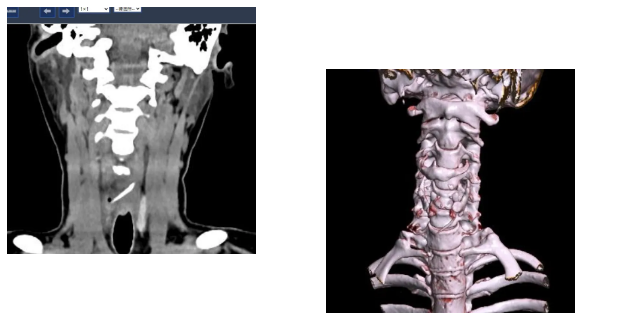

接诊的吕主任详细询问了陈女士的情况,结合她持续加重的咽痛,判断事情没那么简单。立即安排她进行双源CT检查并辅以三维重建技术。检查结果让所有人都捏了一把汗:一根近3公分长的鱼刺,深深卡在食管入口处,不仅位置刁钻,还已经刺穿食道,周围创面出现感染。

消化内镜室迅速启动取刺准备,当胃镜缓缓抵达食管入口时,清晰可见一根长约3cm的鱼刺,正斜斜嵌顿在食管入口的右侧壁,鱼刺尖端已刺入黏膜下层,周围黏膜因刺激出现明显充血水肿。更棘手的是,鱼刺恰好卡在食管入口的生理拐弯处,这个部位是食管与咽喉的衔接点,角度刁钻,内镜难以稳定固定位置。